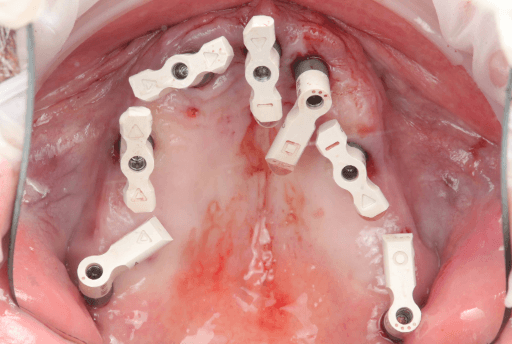

3.2 Post-Surgical Intraoral Scan

Scanning of implant position with scanbodies: Immediately after the implants were placed, the final implant position was captured using Apollo scanbodies and the intraoral scanner (Medit i900).

Apollo scanbodies in place.

Lower arch pre-surgical intraoral situation

3D printed surgical guide with fixation pins

Lower arch with six implants placed

Lower arch surgical procedure. From left to right: Pre-surgical intraoral situation, 3D printed surgical guide with fixation pins, and six implants placed.